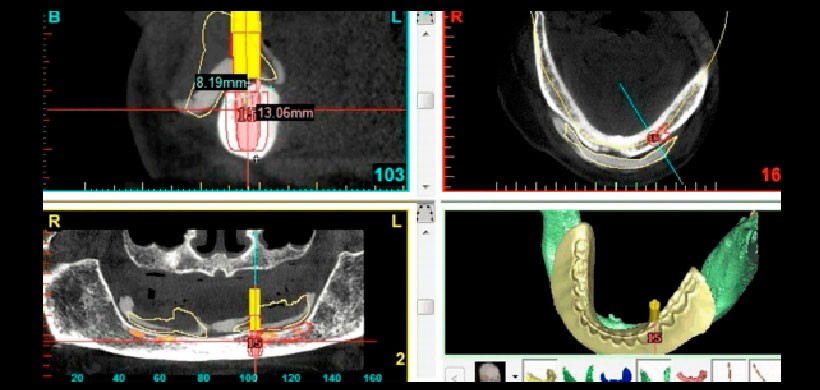

Fig 1. Planificación del tratamiento y la selección del implante mediante un programa informático (SimPlant®) y mediante el uso de la tomografía computarizada de haz cónico (CBCT).